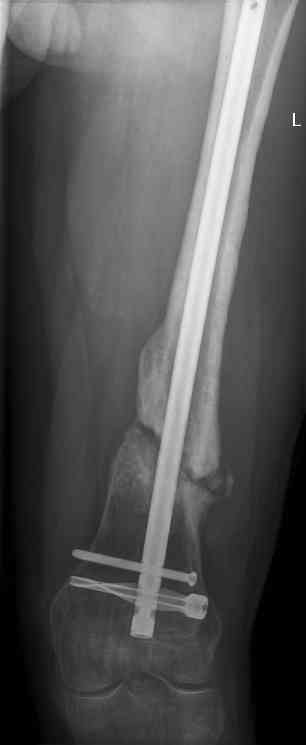

16 yr old boy, high energy motorcycle trauma trauma in July 2005 with:

- hip dislocation + acetabular fracture L

- distal femoral fracture L

- tibial shaft fracture L

- metatarsal fractures L

july 05: LISS femur, LCP plate tibia, double recon. plate post. acetabulum

oct 05: cancellous bone graft femur

aug 06: blade plate + bone graft

nov 06: revision blade plate

feb 07: retrograde nail + bone graft + BMP

may 07: dynamisation nail

sept 07: locking screw removal (max. dynamisation reached)

nov 07: persistant non-union distal femur; other fractures healed uneventfully.

All with gradual/partial weightbearing etc. Currently 50-100% weight bearing, no pain.

Soft tissues are intact. No smoking or diabetes.CRP <2